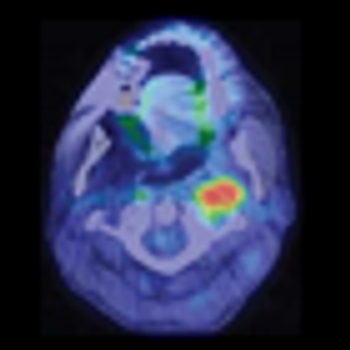

High-risk HPVs may be present more frequently than previously estimated in a variety of head and neck cancers, supporting the use of a combination of methods to detect high-risk strains.

A small retrospective study has identified several biomarkers that were significantly altered in patients with head and neck squamous cell carcinoma. If further validated, these serum biomarkers could facilitate early diagnosis.

Black race did not adversely affect outcomes after receiving radiotherapy for head and neck squamous cell carcinoma compared with white race, according to the results of a study in which black patients made up the majority of enrolled participants.